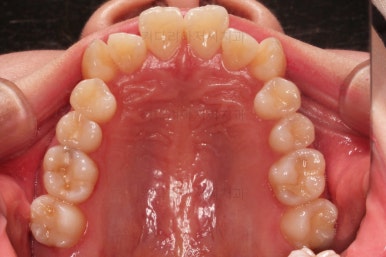

마찬가지로 초진 시 입안의 모습인데요.

전반적으로 약간 삐뚤지만 특히 윗니 앞니가 삐뚤고요.

송곳니는 덧니처럼 튀어나와 보이네요.

그리고 전반적으로 치아가 앞쪽으로 경사되어 있어서 앞니는 뻗친 느낌이 있네요.